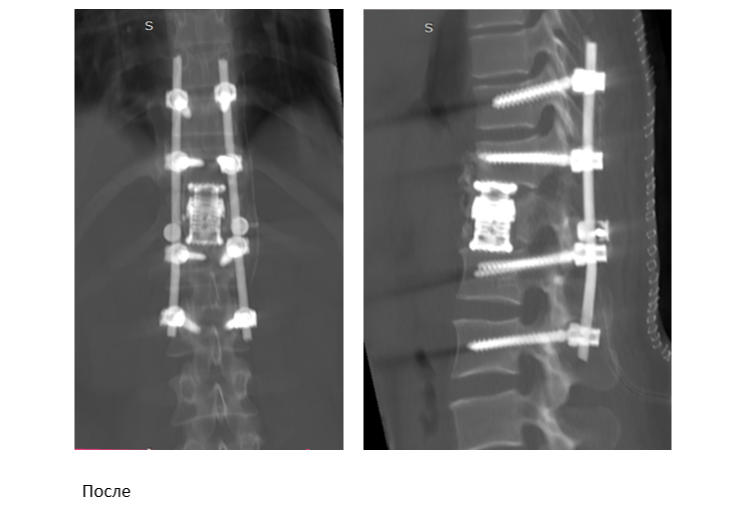

При проведении этого этапа при помощи специальных инструментов хирург удаляет разрушенное и неопорное тело позвонка, добивается получения необходимой подвижности на этом уровне. Далее проводится реконструкция передней колонны позвоночника с помощью современной лифтовой системы — раздвижного телескопического кейджа отечественного производства, который устанавливается вместо Th12 позвонка, тем самым восстанавливается опорная функция позвоночника.

Завершающий этап операции вновь проводится через задний доступ. В этот момент проводится окончательная задняя стабилизация, винты соединяются между собой специальными штангами и фиксируются гайками. В итоге получается очень жесткая циркулярная фиксация (360 градусов). Все три этапа проходили за один день и в общем заняли порядка 8 часов — такие операции возможны благодаря слаженной работе всей хирургической бригады. В команде также работали врач-анестезиолог-реаниматолог Иван Стаценко, операционная медсестра Нина Хромова и медсестра-анестезист Татьяна Массон

Задач у такой хирургии несколько: помимо чисто косметического эффекта, восстановление сагиттального профиля позвоночника позволяет выключить механизмы компенсации (поясничный гиперлордоз и грудной гипокифоз). Гармонизируя сагиттальный профиль позвоночника, специалисты приводят в соответствие параметры баланса: поясничный лордоз, грудной кифоз и разворот таза. Цель была достигнута — врачам удалось вернуть гармонию изгибов позвоночника. Колоссальное перенапряжение мышц уйдёт, а вместе с ним пациентку покинут и сильные мучительные боли.